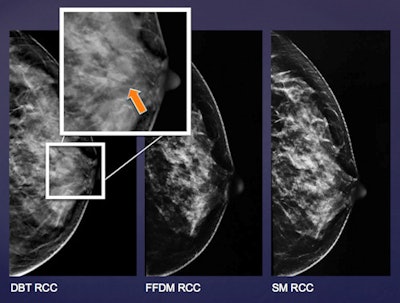

Diagram shows the craniocaudal view of left breast of the same patient in FFDM, synthesized 2D mammography, and selected DBT slice. There is an irregular mass noted at lateral aspect where the spiculations are much easier appreciated by DBT. This lesion was only depicted by DBT and missed by FFDM and mammography during images review. Lesion was a histologically proven invasive ductal carcinoma. All images courtesy of Dr. Lorraine Sinn.Histological proof was the gold standard for differentiating malignant from benign lesions. In the case of no histological proof, ultrasound or MRI was used to problem-solve. A mass was considered "probably benign" when correlated with ultrasound or MR images performed in the same session or the same year. The lesion was also classified as probably benign if it was static compared with previous mammograms and also within the follow-up period.

Diagram shows the left breast of the same patient in FFDM, synthesized 2D mammography, and selected DBT slice. There is a well-defined low-density mass noted at the retroareolar region, which was only depicted by DBT but not by FFDM and mammography during image review. Lesion was confirmed to be a fibroadenoma on subsequent ultrasound with fine-needle aspiration performed.When comparing the lesions with each other, only three out of 13 additional occult lesions in FFDM and two out of six additional occult lesions in synthetic mammography were confirmed to be benign or probably benign lesions. Meanwhile, 32 additional lesions were found only by DBT, 75% of which were confirmed to be benign lesions.